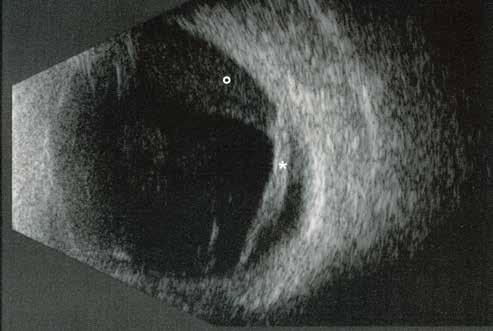

sociated with various retinal changes, such as blunting or lack of foveolar reflex, reduced retinal transparency, crystalline deposits, mild capillary ectasia, slightly dilated venules, foveal atrophy, lamellar or full-thickness macular holes and neovascular complexes.42-44 Neovascular lesions appear to be different from MNV in AMD. They seem to originate from the retinal vasculature, but can access the subretinal space and may develop a retinal-choroidal anastomosis. Sometimes, the membranes resemble markedly ectatic capillaries, which could represent a retinal-retinal anastomosis.43,45,46 The development of a neovascular lesion may occur at an advanced stage of the pathological process and lead to frequent vision loss. Neovascular lesions are associated with macular edema, subretinal hemorrhages before progressing to a cicatricial and fibrotic stage. (Figure 9 and 10). Therefore, intervention may potentially be beneficial in the early stages of the disease.46

Figure 9. Multimodal imaging of bilateral macular neovascularization and idiopathic macular telangiectasia. MultiColor image (A) revealing the hemorrhage at the posterior pole and the dilated telangiectatic perifoveal vessels. Blue and green fundus autofluorescence (B and C) showing the retinal pigment epithelium changes. Indocyanine green angiography (D and E) and fluorescein angiography (F and G) displaying the macular neovascularization with leakage in the late phase. OCT (H and I) showing the outer retinal atrophy, the subretinal hyperreflective material and the internal changes related to the Müller cell degeneration. MultiColor image (L) revealing the dilated telangiectatic perifoveal vessels and the multiple golden crystalline refractile deposits. Blue and green fundus autofluorescence (M and N) showing the retinal pigment epithelium changes with the loss of macular pigment. Fluorescein angiography (O and P) and indocyanine green angiography (Q and R) displaying the macular neovascularization. OCT (S and T) revealing the outer retinal atrophy, the subretinal hyperreflective material and the full thickness macular hole due to the Müller cell degeneration.